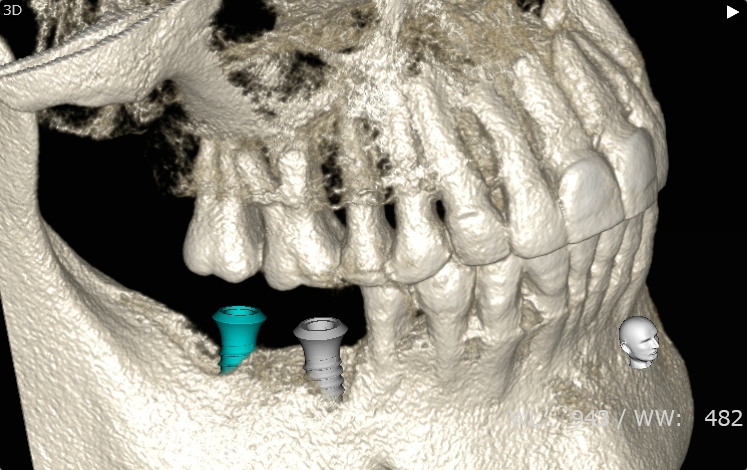

Case7

術前

術中

術後

| 治療名 | 抜歯即時インプラントとソケットリフトによる上顎臼歯部の修復症例 |

|---|---|

| 治療説明 |

歯の根が破折していたため抜歯が必要となり、患者さんとご相談のうえ、インプラントによる治療を選択しました。 ただし、インプラントを支える骨の高さが不足していたため、**上顎洞に骨を足す“ソケットリフト”**を併用し、安全にインプラントを埋入しました。 |

| 治療回数・期間 | 約3ヶ月 |

| 副作用とリスク |

・入れ歯や従来のブリッジと比べて、治療期間が長くなる傾向があります。 |

| 料金(税込) | 小規模GBR:110,000円 ソケットリフト:165,000円 インプラント一次手術:220,000円 二次手術:55,000円 上部構造〈セラミック〉:165,000円 合計:715,000円 |